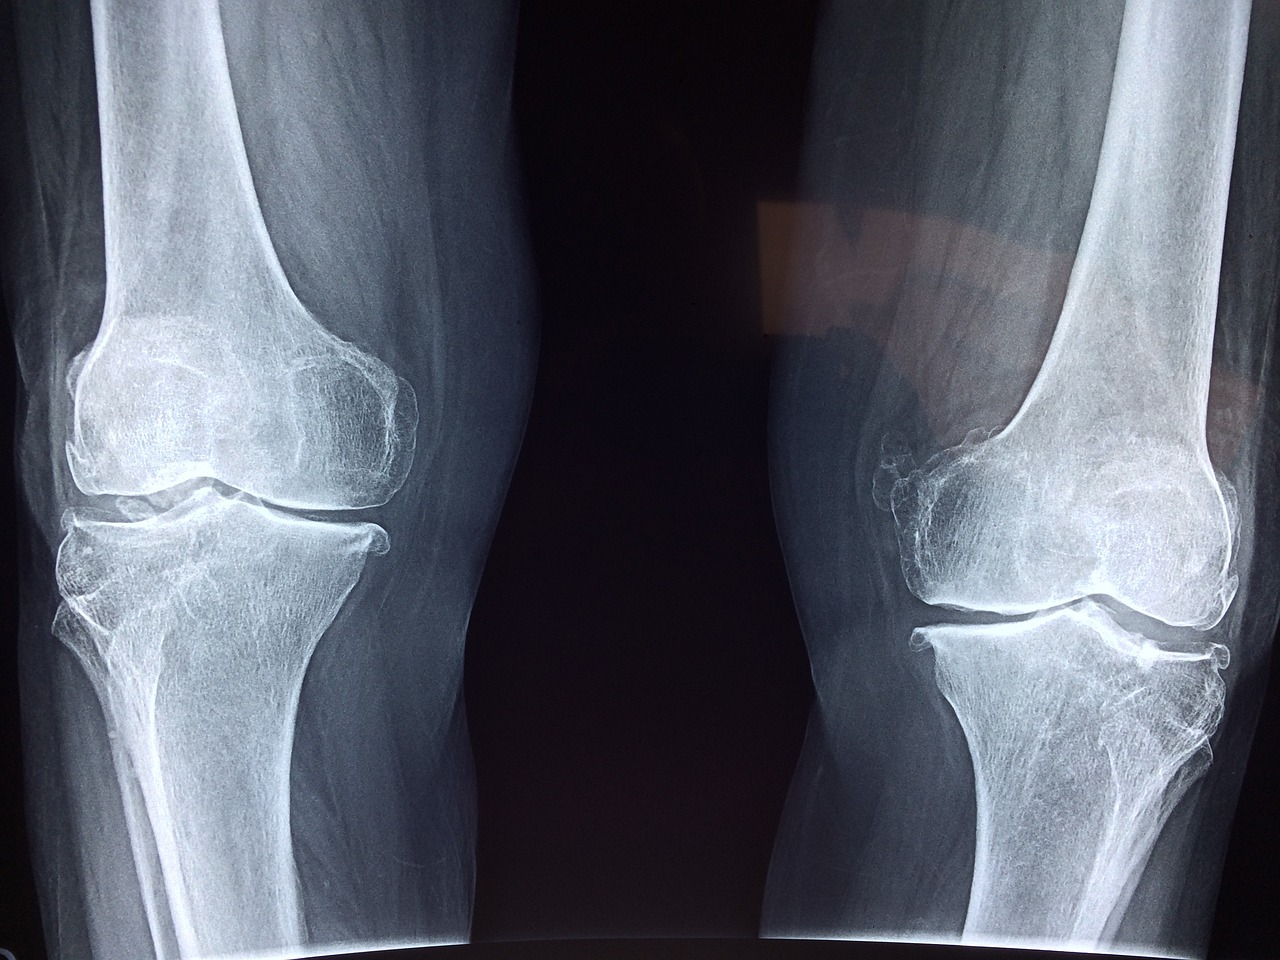

관절 건강은 나이가 들수록 신경 써야 할 중요한 건강 요소입니다. 관절은 신체의 움직임을 가능하게 하는 역할을 하며, 이를 지키기 위해서는 올바른 식습관, 적절한 운동, 그리고 필요한 영양제를 섭취하는 것이 중요합니다. 아래에서는 관절 건강을 유지하고 개선하는 데 도움을 줄 수 있는 방법들을 소개합니다.

2. 관절에 좋은 운동

운동은 관절의 유연성과 강도를 유지하는 데 필수적입니다. 그러나 관절에 무리가 가지 않는 운동을 선택하는 것이 중요합니다.